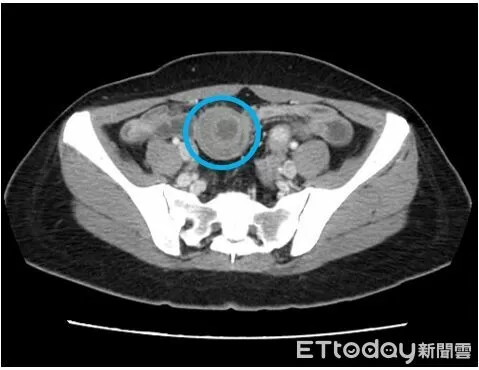

▲王女的小腸套疊得如望遠鏡,卻驚人發現腸套疊的元凶,竟是小腸黏膜下層一顆三公分罕見腫瘤。(圖/平等澄清醫院提供)

平等澄清醫院腸胃科黃一修醫師表示,經安排腹部電腦斷層檢查,影像顯示小腸出現「標靶徵象」,診斷為「腸套疊」。立即啟動跨科會診,將患者轉由一般外科醫師王志浩接手,進行緊急微創手術治療。

醫師王志浩施行「腹腔鏡部分小腸切除術加吻合術」時發現,在距離王女迴盲瓣約150公分處,有一段小腸竟像收納望遠鏡般,套入了另一段遠端腸道中。而這場腹內災難的元凶,是一顆位於小腸黏膜下層、大小約3x3公分的堅硬腫塊。這顆腫塊充當了套疊的「引導點」,導致腸道蠕動時將自身捲入。